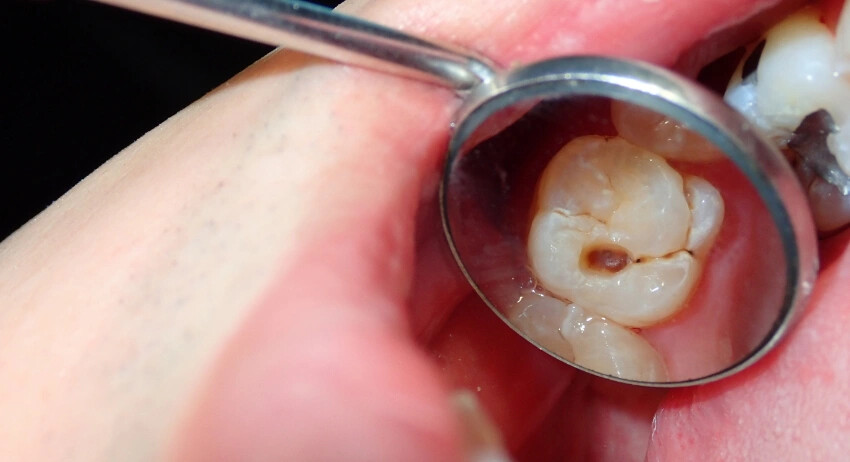

Cavities

Cavities are among the most popular periodontal dentist problems because almost every child may have to face them. Cavities are smaller holes that are formed in the center of your teeth because of bacterial infection (plaque). The major cause is the weak enamel that leads to plaque and plaque leads to cavities.

When Does Cavities Need a Dentist?

Cavities always need a good dentist because it cannot be fixed by home remedies. If you are having a dental cavity then you must be aware of finding a good dentist guide.